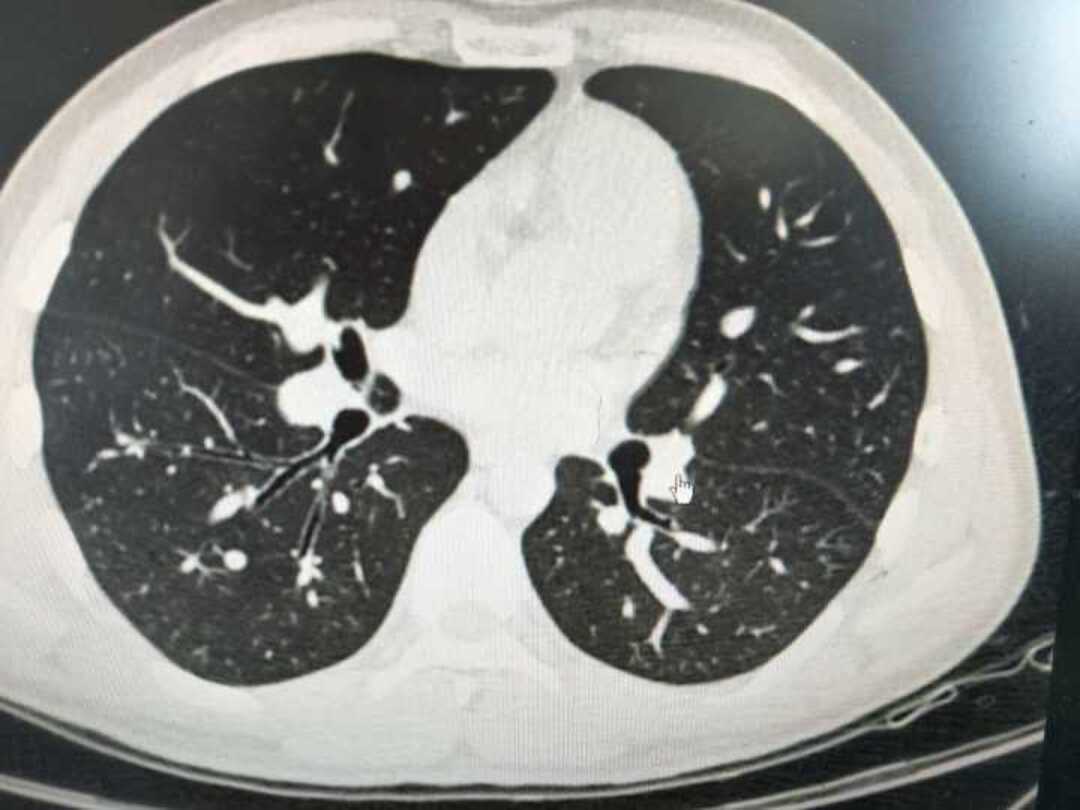

肺磨玻璃结节的ct诊断